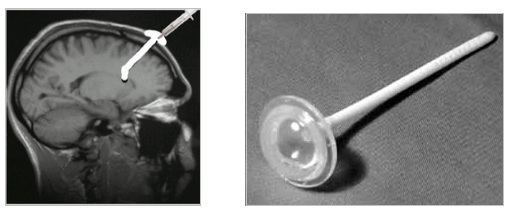

Τι είναι οι εμφυτεύσεις reservoir σταθερής ενδοκοιλιακής έγχυσης φαρμάκων

Η ενδοκοιλιακή έγχυση μορφίνης ενδείκνυται σε ασθενείς με καρκινικό πόνο ανθεκτικό σε κάθε μορφή συντηρητικής αντιμετώπισης. Η μορφίνη εγχύεται στο εγκεφαλονωτιαίο υγρό μέσω καθετήρα που εμφυτεύεται στο μετωπιαίο κέρας των πλάγιων κοιλιών του εγκεφάλου και συνδέεται με ένα ρεζερβουάρ Ommaya που τοποθετείται υποδορίως κάτω από το δέρμα του τριχωτού της κεφάλης. Το reservoir ανατροφοδοτείται με φάρμακο σε τακτά χρονικά διαστήματα. Μέσω του συστήματος δύναται να χορηγηθούν και χημειοθεραπευτικοί παράγοντες.